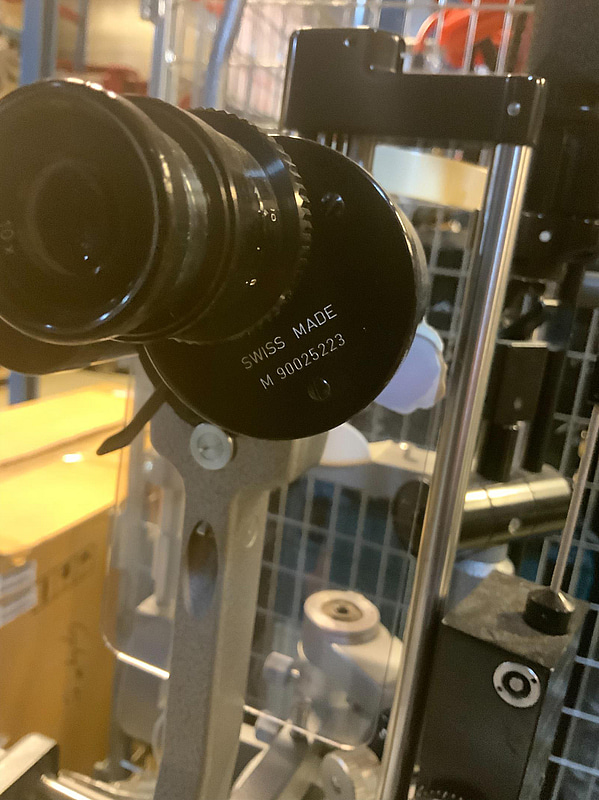

B90025223

M90025223

R90028569